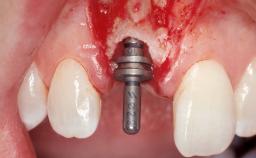

Late Flapless Placement of an Implant in a Maxillary Left Central Incisor Site

Type of Implants One-Piece

Attachment One-Piece

Placement Protocol Early or late implant placement

Bone Volume Deficient horizontally, requiring prior grafting